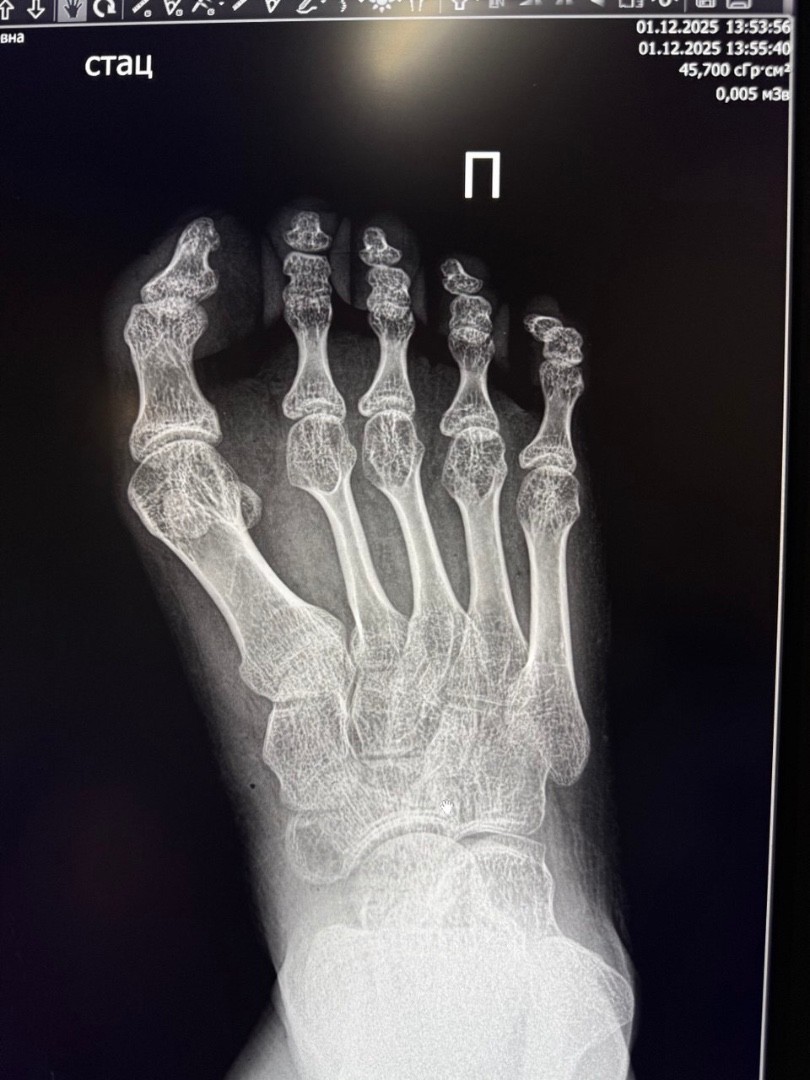

• В Елецкой детской больнице проведена сложная операция 17-летней пациентке с детским церебральным параличом

У девушки была приобретенная деформация первого пальца правой стопы 3 степени, вызывавшая боль и затруднения при ходьбе.

Заведующий травматологическим отделением Махач Алиев выполнил реконструктивное вмешательство по методикам Шеде-Брандеса и Арина. Реабилитация проходит успешно.